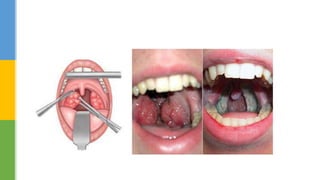

Oropharyngeal :Structure tonsillar hypertrophy, adenoid hypertrophy

 Tonsillectomy ± adenoidectomy

Oropharyngeal :Structure tonsillarhypertrophy, adenoid hypertrophy craniofacial abnormalities  Tonsillectomy ± adenoidectomy  Uvulopalatopharyngoplasty (UPPP)  maxillomandibular advancement surgery  Hyoid Suspension Upper airway surgery